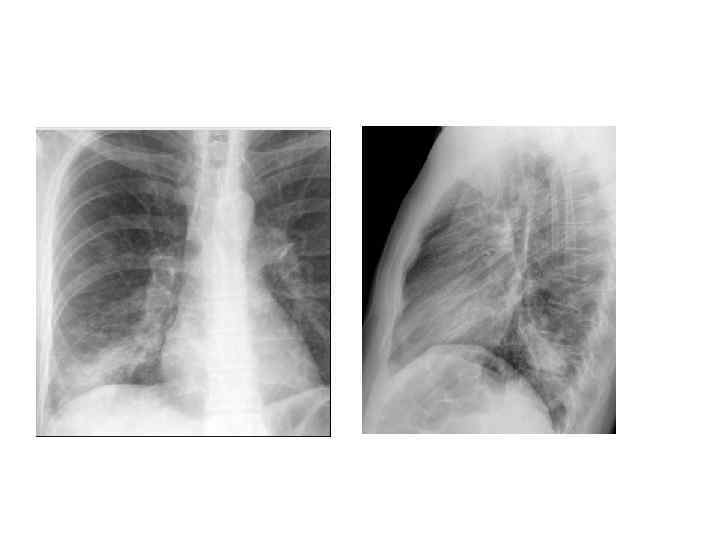

Рентгенологическая диагностика ВП • Рентген ОКГ является обязательным методом подтверждения диагноза пневмонии • Рентген ОКГ в двух проекциях должен быть проведен быстро при клиническом подозрении на пневмонию • Рентгенологический признак пневмонии – появление очаговой инфильтрации в легких

Критерии тяжелого течения ВП • • • Двух- и многодолевое поражение ОДН (Ра. О 2 < 60 мм рт. ст. или Sat 02 < 90%) Шок (снижение АД <90/60) ОПН Нарушение сознания

Дифференциальный диагноз • Туберкулез (обязательно 3 -кратная микроскопия мазков мокроты на БК с окраской по Цилю-Нильсену) • ТЭЛА • Центральный и периферический рак легкого • Септическая пневмония у пациентов с ИЭ ТК (как правило у инъекционных наркоманов)